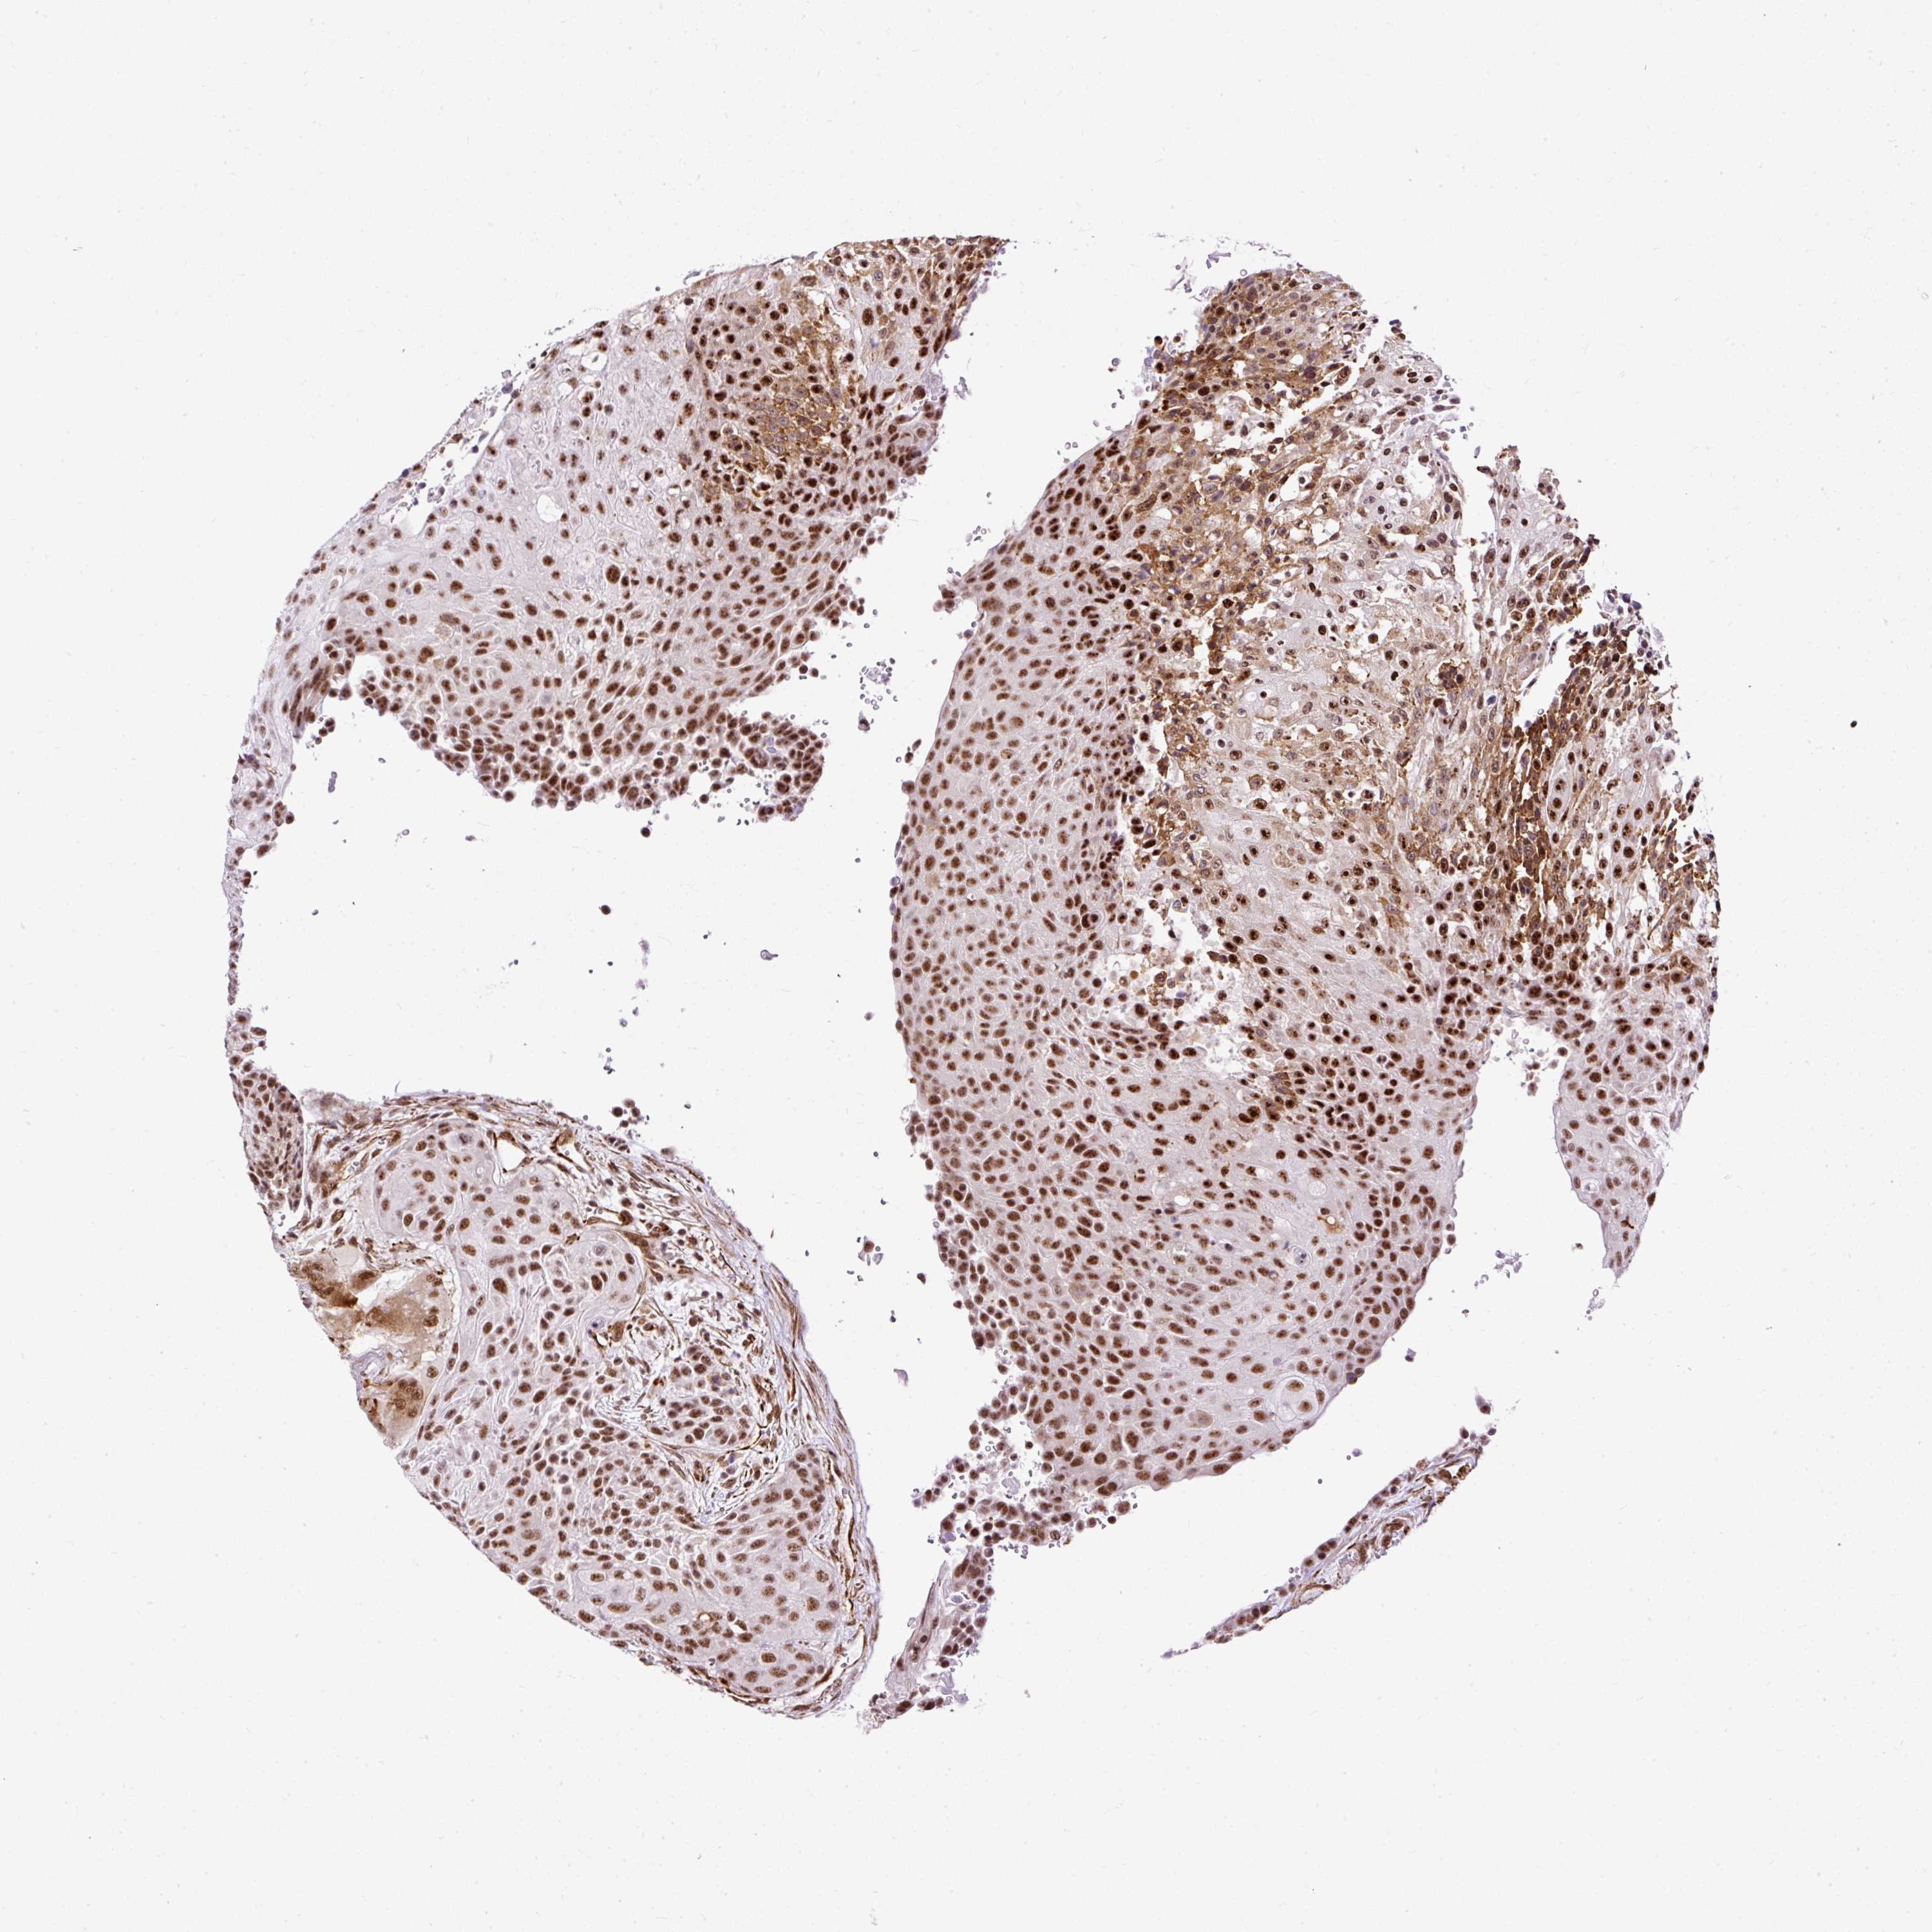

UROTHELIAL CANCER - Protein expressioni

A mouse-over function shows sample information and annotation data. Click on an image to view it in a full screen mode. Samples can be filtered based on level of antibody staining by selecting one or several of the following categories: high, medium, low and not detected. The assay and annotation is described here.

Antibody stainingi

Antibody staining in the annotated cell types in the current human tissue is reported as not detected, low, medium, or high, based on conventional immunohistochemistry profiling in selected tissues. This score is based on the combination of the staining intensity and fraction of stained cells.

Each image is clickable and will lead to virtual microscopy that enables deeper exploration of all samples and also displays staining intensity scores, fraction scores and subcellular localization as well as patient and tissue information for each sample.

Antibody HPA045663

Antibody HPA051631

Staining

High

Medium

Low

Not detected

Intensity

Strong

Moderate

Weak

Negative

Quantity

>75%

75%-25%

<25%

None

Location

Nuclear

Cytoplasmic/membranous

Cytoplasmic/membranous,nuclear

Urothelial carcinoma, High grade

Urothelial carcinoma, NOS

Urothelial carcinoma, Low grade